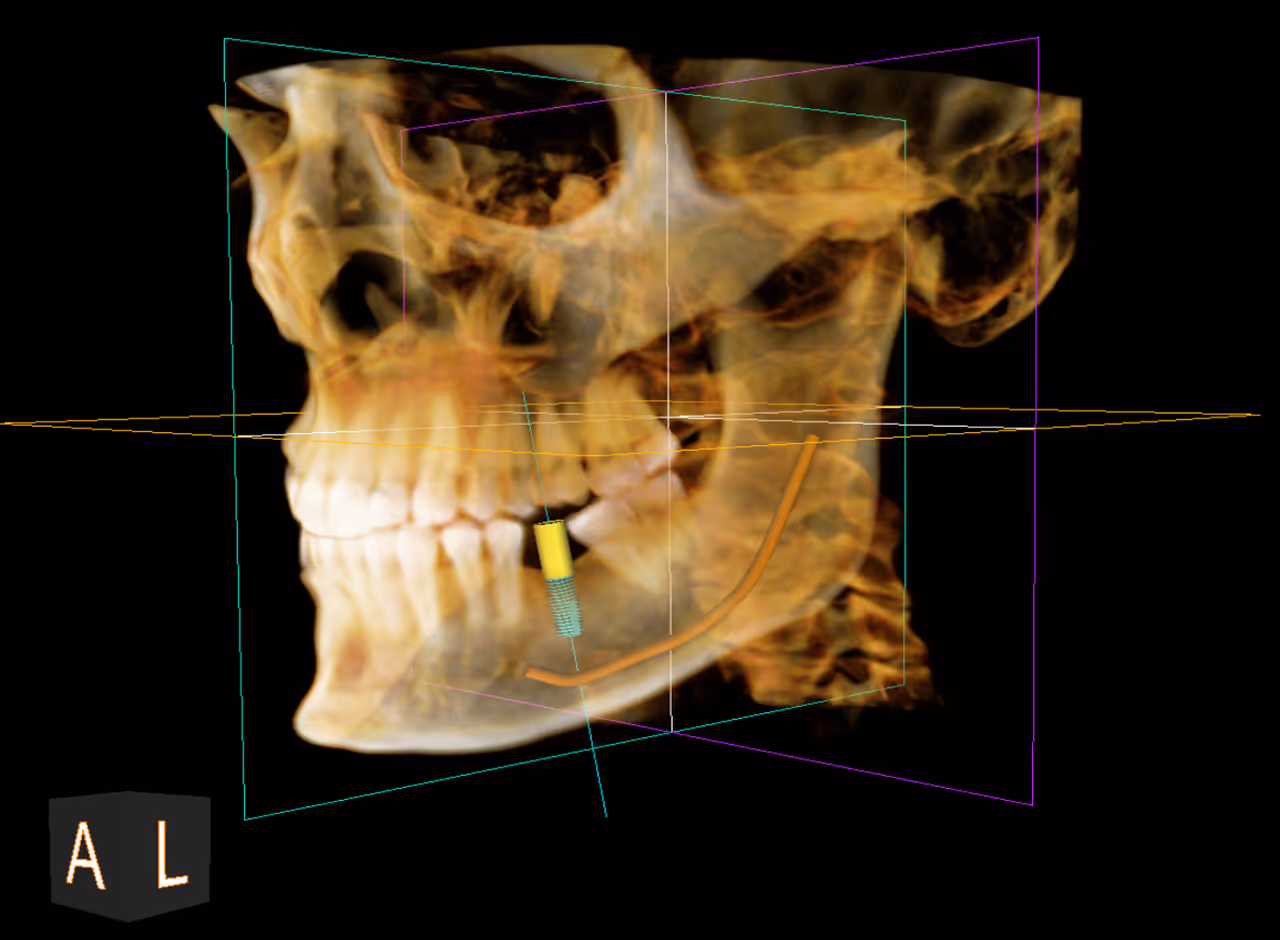

Our office utilizes the latest technology and equipment to provide better, more precise care. CBCT or 3D CT dental scans are now the standard of care for dental implant planning and surgery, wisdom teeth extractions, and root canal therapy.

A 3D CT dental scan, also known as Cone Beam Computed Tomography (CBCT), is an advanced, low-radiation imaging technology that creates detailed, 3D digital models of teeth, jawbones, nerve pathways, and soft tissues in seconds. It provides superior accuracy over traditional 2D X-rays for planning implants, oral surgery, and diagnosing complex dental issues.

- Dental Implant Planning: It is considered the gold standard for measuring bone density and volume to ensure safe and accurate implant placement. Learn more about our approach to dental implants.

This advanced imaging allows Dr. Shawn Cohen to plan treatments with precision. Learn more about his experience and approach on the Meet Dr. Cohen page.